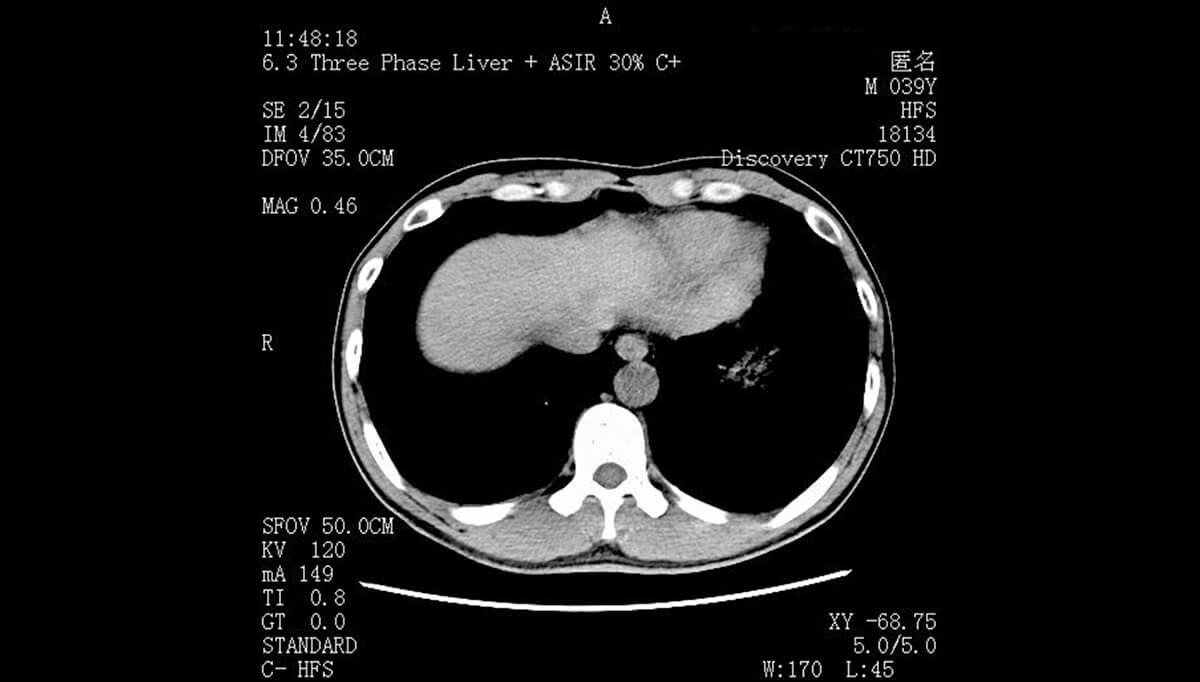

从技术参数来看,4K医疗显示器(分辨率3840×2160)的像素密度是传统2K显示器的4倍,能呈现更多影像细节。在放射科日常诊断中,肺部CT的微小结节、乳腺钼靶的细微钙化点,或是骨科X光片的骨小梁结构,这些易被低分辨率显示器忽略的细节,在4K屏幕上能清晰呈现。有临床数据显示,使用4K医疗显示器后,肺部微小结节检出率提升,有效降低漏诊风险——这是高分辨率最核心的诊断价值。

同时,4K医疗显示器的宽色域和高色准度,能更真实还原影像色彩。在病理科的数字切片观察中,细胞的染色差异、组织的边界轮廓,都需要精准的色彩呈现来辅助判断;皮肤科的皮肤镜影像诊断中,色素痣的颜色渐变、血管分布细节,也依赖4K屏幕的色彩表现力。此外,4K显示器支持更大尺寸屏幕下的分屏显示,医生可同时对比同一患者的历史影像与当前影像,或在同一屏幕上查看CT、MRI等不同模态影像,无需频繁切换窗口,大幅提升诊断效率。